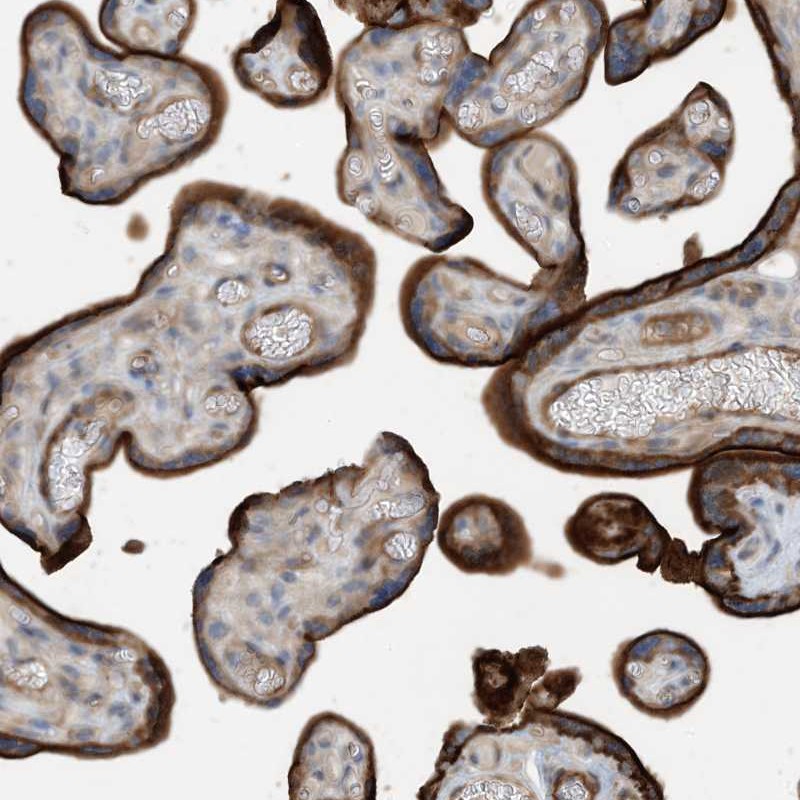

Immunohistochemical staining of human placenta shows strong cytoplasmic positivity in trophoblastic cells.